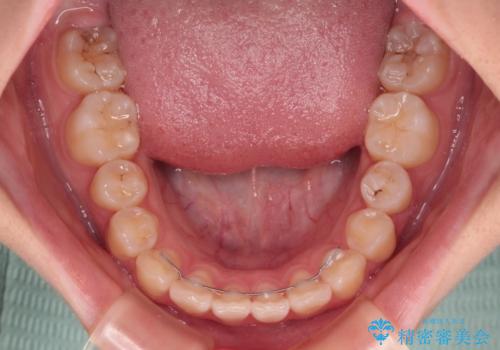

- 上下前歯のねじれを気にして来院された患者様です。

ワイヤー矯正でもマウスピース矯正でも対応可能でしたが、マウスピース矯正の自己管理が面倒であること、上顎前歯の捻転が著しいことから、ワイヤー矯正での治療を希望されました。

- 11ヶ月